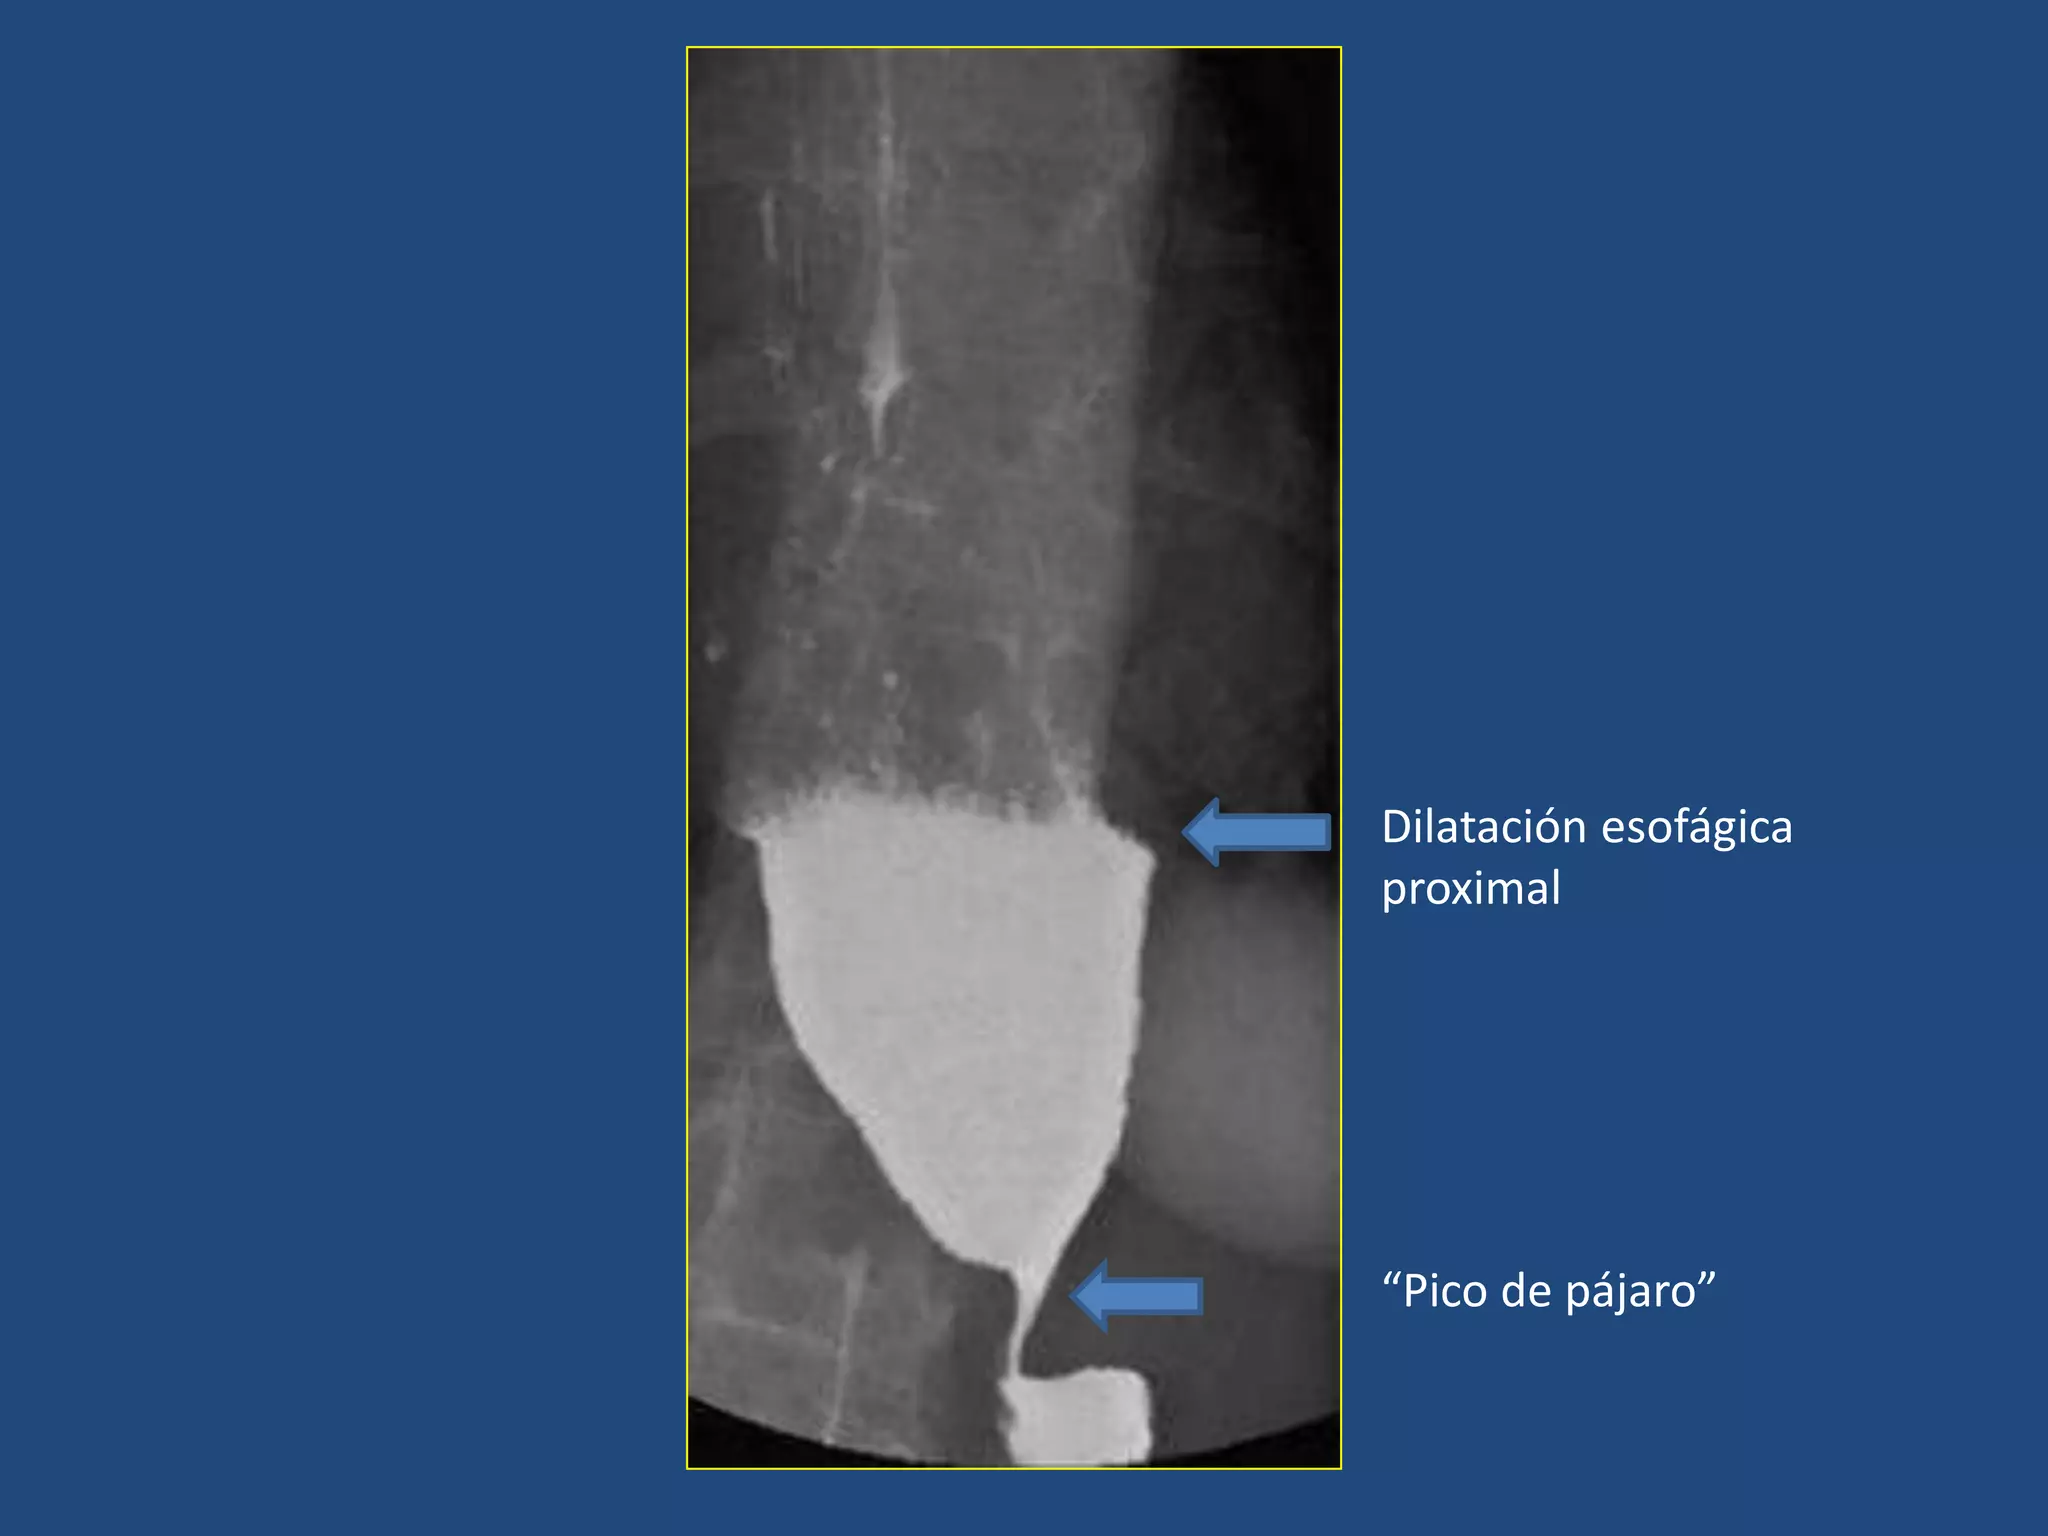

• Acalasia:

Hipertonía del esfínter esofágico inferior

Hallazgos:

Imagen en “pico de pájaro”

Dilatación esofágica hacia proximal

ESÓFAGO: TRASTORNOS DE LA MOTILIDAD

Dilatación esofágica

proximal

“Pico de pájaro”